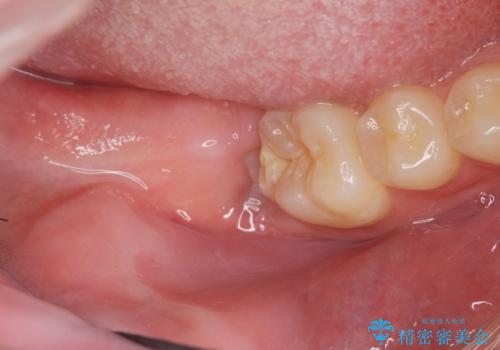

左下の親知らずが腫れた感じがする。

斜めに生えてきている親知らずを抜きたい

左の親知らず抜歯したい。

右下親知らず抜きたい。